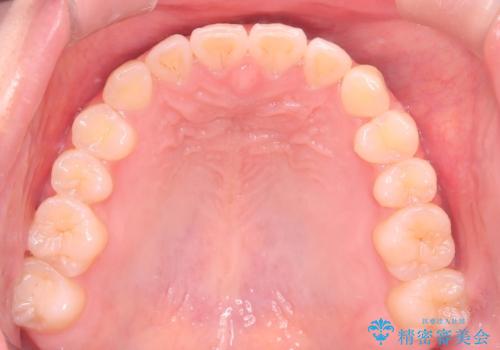

最初は、一番後ろの奥歯でしか噛んでいない状態で、上下の前歯の先端がちょうど当たる切端咬合でした。

口腔習癖の改善及び、ワイヤー矯正にて歯列の平坦化を行うことで咬合を確立することができました。

保定中の後戻りを防ぐため、口腔習癖の改善が必要です。